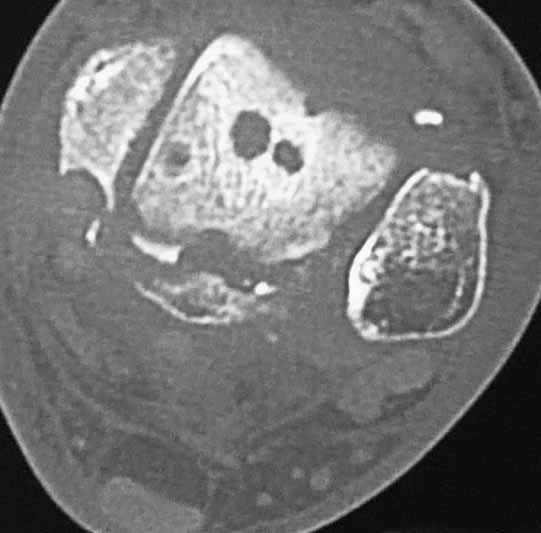

Уважаемые коллеги. Не так давно на форуме коротко обсуждались возможные последствия трансартикулярной фиксации голеностопного сустава при переломовывихах лодыжек.

На днях довелось увидеть КТ после удаления спиц. Картинки наглядные и, практически, не нуждаются в комментариях. Одна из спиц, кстати, проходила через фрагмент заднего края.

Картинки наглядные и, практически, не нуждаются в комментариях. Одна из спиц, кстати, проходила через фрагмент заднего края

Снимки являются доказательством важности защиты суставного хряща от грубой интервенции, и особенно от тех неудачных многочисленных попыток фиксации спицами, когда спицы оставляют на поверхности сустава непоправимые следы. Понятно, что повреждение целости хряща приводит к развитию хондролизиса, артрозу и т.д....

Но прежде, чем давать окончательную оценку, надо разобраться, почему была выбрана трансартикулярная фиксация. И применение транс-артикулярной фиксации можно оправдать, когда метод применяется временно ради спасения всего сустава, или когда ситуация не позволяет провести традиционную фиксацию. Тогда можно пойти на жертву, т.е. на повреждения небольшого участка хряща.

Понятно, огромные “дырки” в суставе не от хорошей жизни, хотя на самом деле “увеличенная картина” на КТ срезах может оказаться банальным проколом от 1,2 или 2 мм спиц. Большие неприятности, когда спицы находятся долго, и когда лизис вокруг спицы принимает большие размеры. А так - не стал бы драматизировать единичные спицы, установленные на короткое время, потому что такие “интервенции” сустава у большинства больных проходят без клинических проявлений.